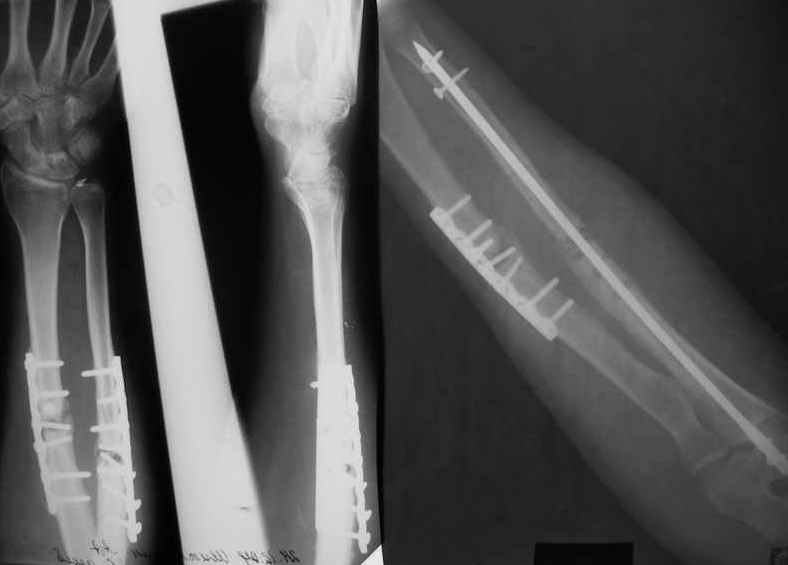

Уважаемые коллеги!Доводим до Вашего сведения наш скромный опыт применения блокирующего остеосинтеза локтевой кости (4случая), четверо пациентов с ложными суставами локтевой кости. Во всех случаях оперировали открыто с костной аутопластикой.Технических проблем введения штифтов не было. В одном случае отвалилась резьбовая часть спицы при прокс. блоке (оставлена как блокирующий винт). Дистальное блокирование осуществляли используя вместо кондуктора сп. Киршнера изгибая ее конец о край кондуктора на необходимую длину до отверстий. Наши первые впечатления классные. Очень быстрая функциональная реабилитация без гипса и консолидация через 2 мц. На представленных фотографиях двое пациентов.Тот, у которого якобы не срастается лучевая кость на АО пластине, уже катался на горн. лыжах, а сейчас опять уехал на Эльбрус -экстремал ,,,нов. С уважением Нагога Александр, ортопедическая клиника ОРТО, Самара.

Эта конкретная больная на пятый день после операции мыла дома пол (муж - хирург, не мог же он этим заниматься :-)

А движения как раз начинаются максимально рано, на следующий день, включая ротацию - больших ран ведь нет, сильно не болит - в приложении картина в день снятия швов.

При *закрытом* интрамедуллярном остеосинтезе - это редкость. Где-то на 60 больных есть одно несращение лучевой кости (рентгенологическая находка, клинических проявлений нет) - синтез получился с удлинением.